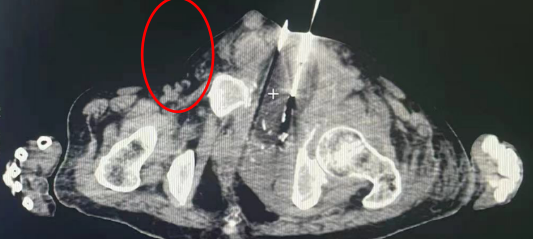

患者男性,54岁,既往肝癌,于我科行规律介入栓塞治疗,肝内病灶控制良好,近1年前发现左侧耻骨转移,病灶逐渐增大,患者疼痛难忍,置入止疼泵后仍无法较好缓解疼痛。既往热消融治疗2次,患者无法耐受手术疼痛,同时因怕损伤周围的膀胱、输尿管、神经、血管等正常组织,无法消融彻底,肿瘤生长迅速。在此次氩氦刀冷冻消融治疗中,患者无疼痛及不适感,配合良好,病灶消融完全。除了彻底破坏肿瘤细胞外,同时,因氩氦刀能特异性选择肿瘤组织进行消灭而不损伤正常的组织,而使肿瘤得以充分的消灭。在经过氩氦刀治疗后,患者白介素-2,白介素-6,肿瘤坏死因子和特异性抗体的水平分泌增加,同时起到免疫抗肿瘤的作用。

△肿瘤冷冻后形成“冰球”形成“冰球”